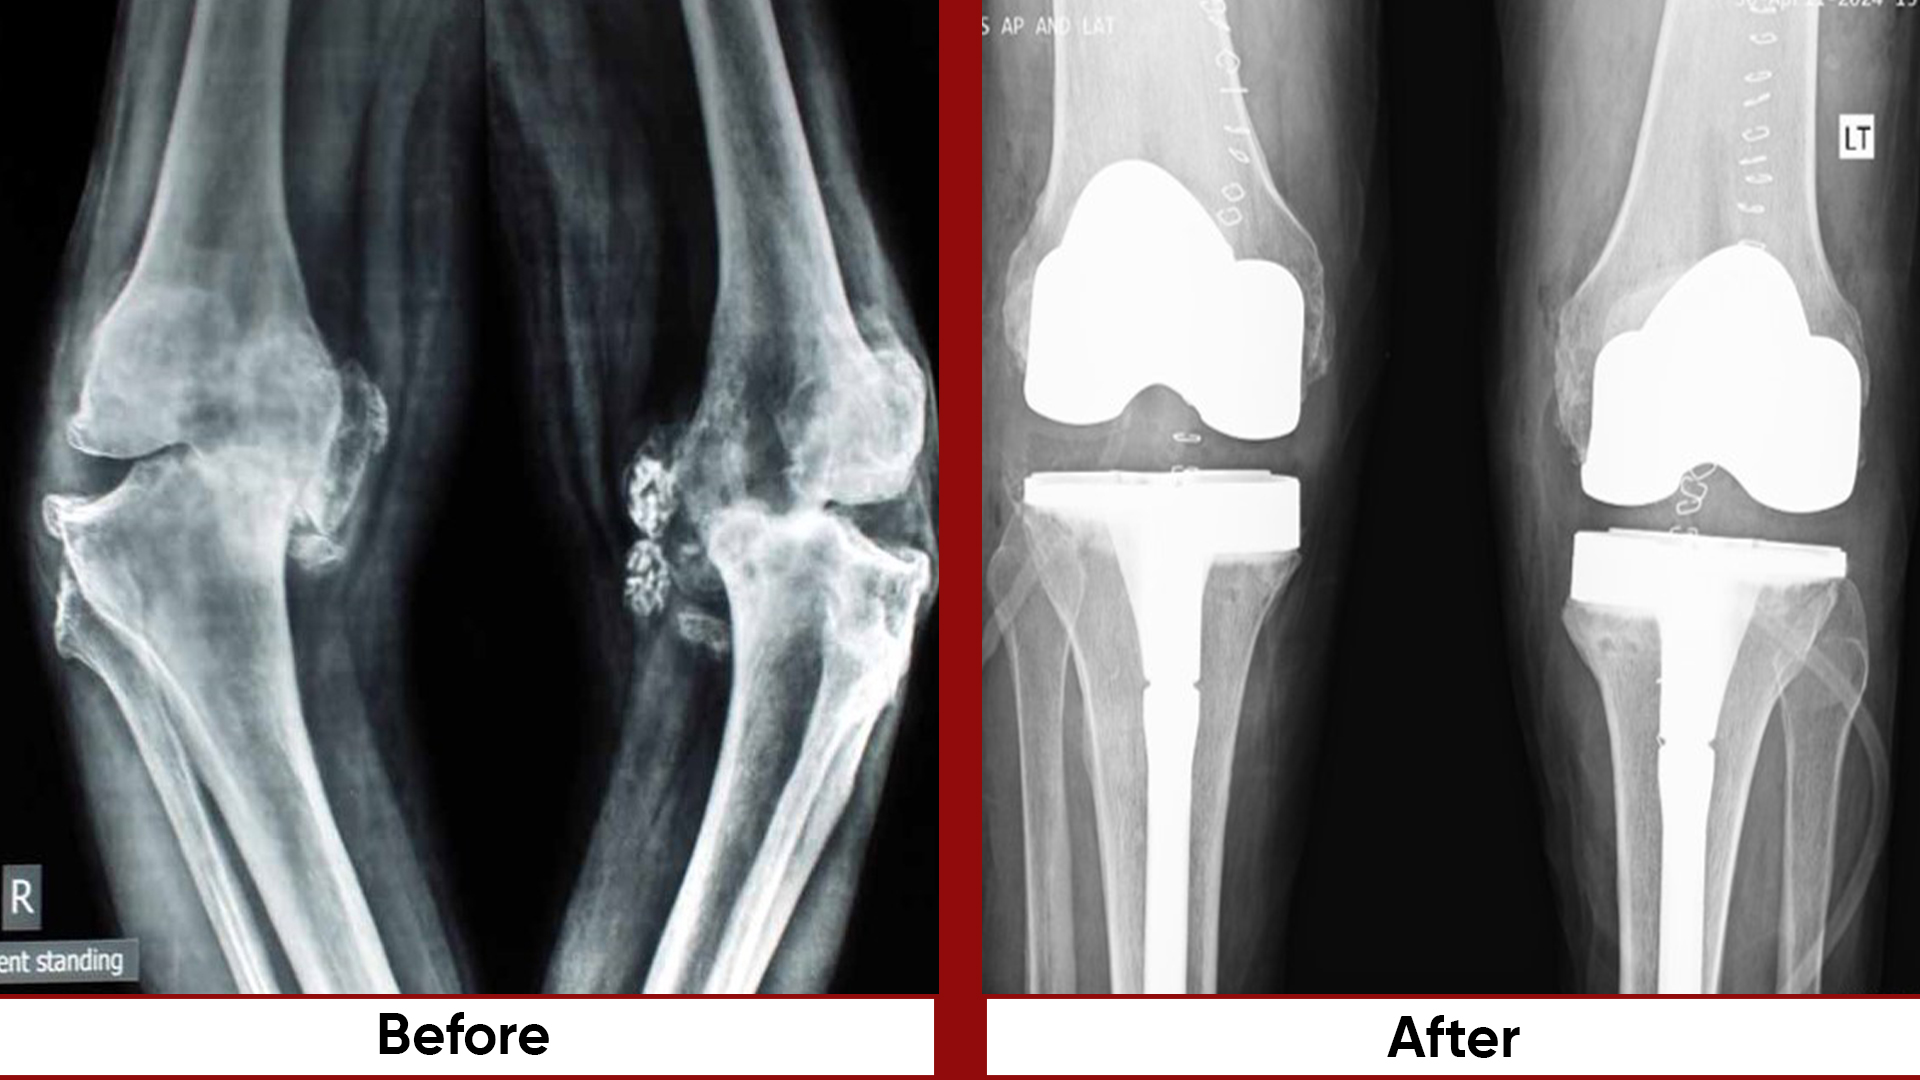

• Total Knee Replacement (TKR)

• Arthroplasty